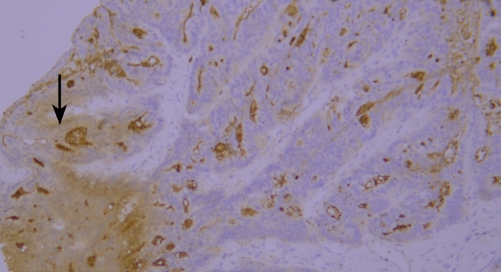

典型实例:

人胎盘组织石蜡切片CD34染色:HRP直标二抗显色结果为弱阳性、低背景;多聚物酶标记二抗显色结果为强阳性、背景干净、对比明显。

结论:不同的显色系统会有不一样的显色结果。多聚物酶标记二抗比普通的HRP直标二抗灵敏度更高,背景更干净,对比更明显。